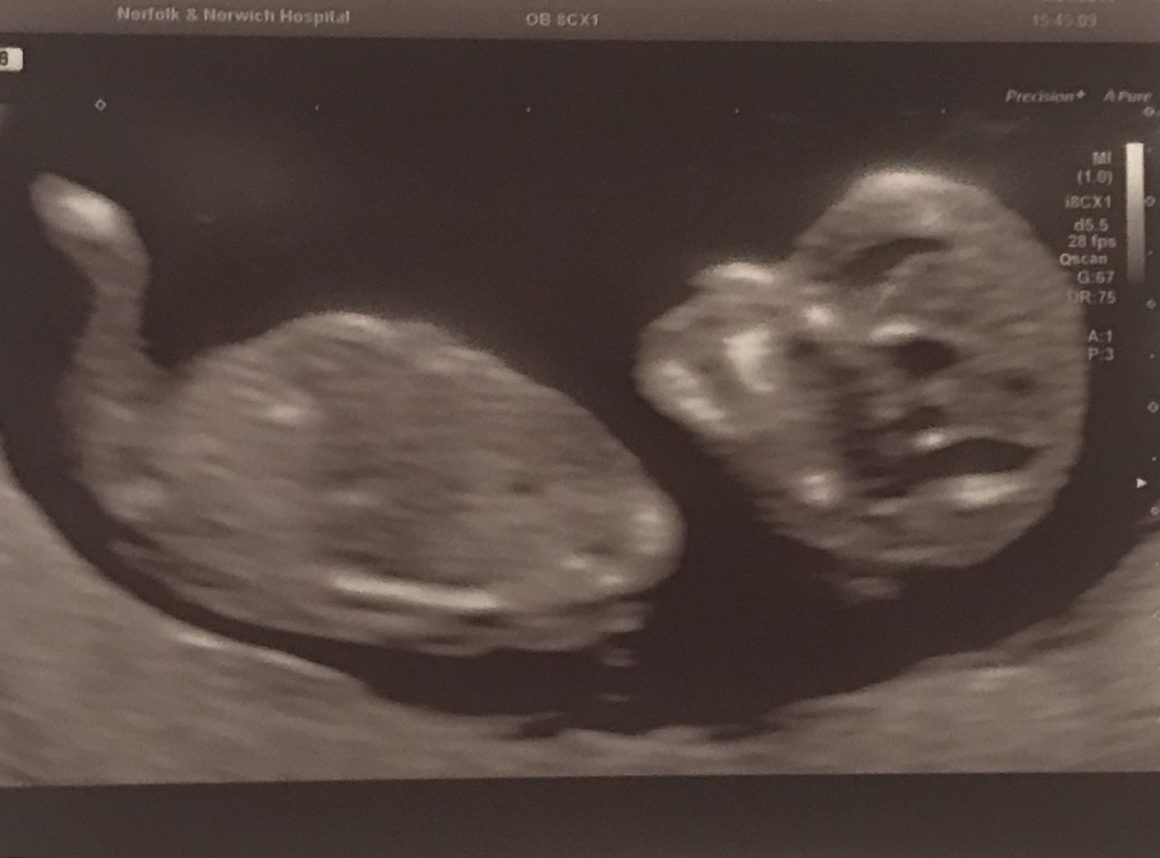

We went for our 20 week scan on March 14th. I remember sitting in the waiting room with Sam both feeling so nervous and excited at the same time.

After a short wait, it was time. With all of the abnormality checks completed, I watched Sam in tears with the news that everything was ok, a little part of the baby was spotted and we were told we were expecting a little boy!